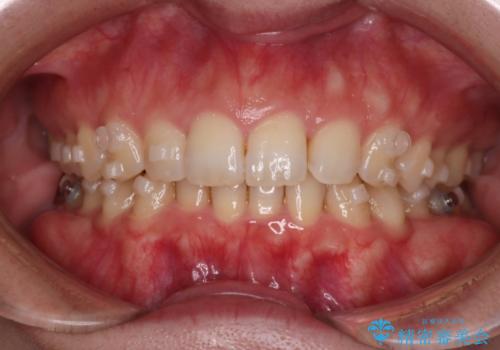

- 下の歯のがたつきを主訴に来院されました。

下の歯のがたつきと右の奥歯の噛みあわせ改善するために治療計画を立てることにしました。

右側臼歯部の咬合改善のために、臼歯部のみ部分的なワイヤー矯正を行い、咬合改善がみられてからインビザラインにて全体的な矯正を行なっていく治療計画を立てました。

噛み合わせをよくするために、ワイヤー矯正とインビザライン矯正のどちらの期間も必要な箇所にゴム掛けを行いながら治療を行いました。

下の前歯のがたつき改善にはIPR(歯と歯の間を削る処置)を行いました。

ゴム掛けを頑張っていただいたので、噛みあわせも改善され綺麗な歯並びになりました。